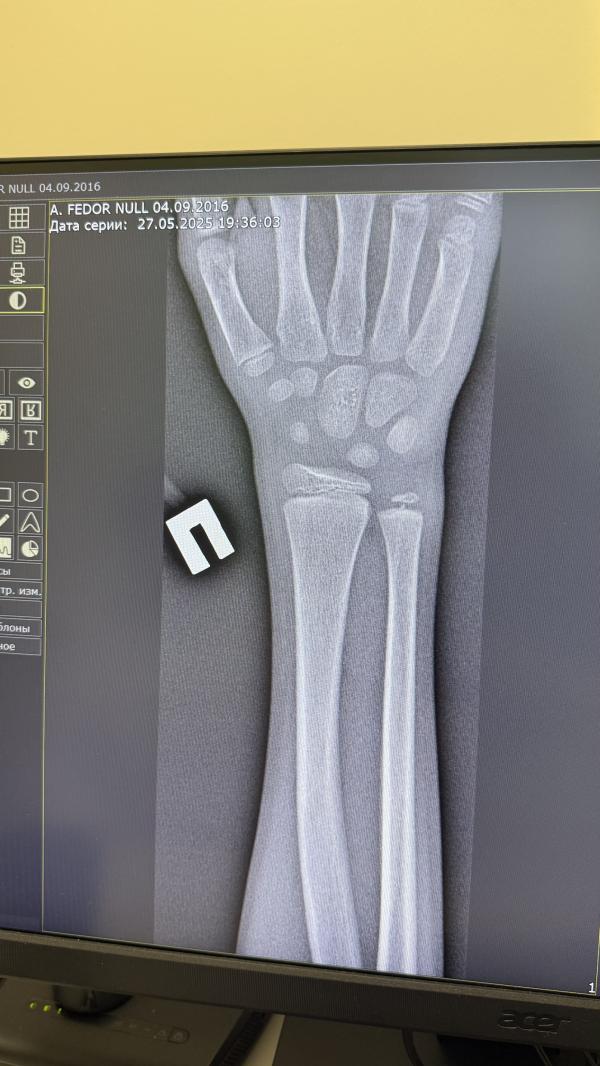

Помогите! Советом или контактом хорошего травматолога в Москве. Сын на тренировке по футболу неудачно отбил мяч рукой. Тренер уверил, что перелома нет, сын плакал только в самом начале, когда я его забрала уже просто повсхлипывал. Рука не опухла, не посинела, но болит. Мы в воскресенье улетаем в Египет и я конечно же решила перестраховаться и поехала в травмпункт. Врач смотрела снимок, потом стала смотреть руку, нажимать на место где болит, сравнивать с другой (как по мне внешне изменений нет) и говорит: Гипс! Я в а…е, спрашиваю: у него перелом? Ее ответ: Повреждение ростковый зоны. В заключение указывает: Перелом нижнего конца лучевой кости закрытый. Подтвержден. Закрытый перелом (эпифизиолиз) дистального отдела правой лучевой кости без смещения. Гипс наложили. Я сомневаюсь, что сделали все правильно, и вдруг можно ограничится пластиковой лангеткой. Как быть? Ехать в другой травмпункт? Чуть позже: в четверг/пятницу? Искать травматолога? Ааа….мой мозг кипит….

Ну ведь понимаете, что врачи тоже разные бывают, к сожалению((( особенно в бесплатной медицине- все поставленно на конвейер. травмпункт районный: бешенный поток, она даже здравствуйте нам не сказала и смутило, что она долгоооо смотрела снимки, встала, подошла к нему- нажимала/крутила/вертела/опять снимки смотрела и потом только решила, что гипс. Вдруг просто перестраховывается.

@chipa_bu, возможно, но сын говорит у детей это считается переломом. Оставьте пока гипс. Контрольный снимок через 2 недели и там уже решат.

А другая проекция есть? И вторая рука для сравнения?